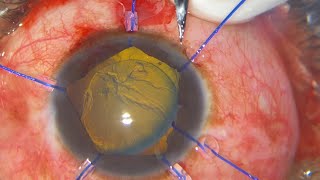

Combined phaco and vitrectomy for rhegmatogenous retinal detachment Combined phaco-vitrectomy for white cataract and total retinal detachment

Combined phaco and vitrectomy for rhegmatogenous retinal detachment Combined phaco-vitrectomy for white cataract and total retinal detachment